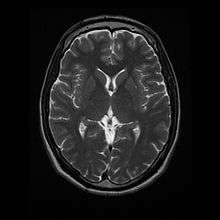

Normal axial T2-weighted MR image of the brain.

- T2: CSF is light, but fat (and thus white matter) is darker than with T1. T2 is useful for visualizing pathology.[14]